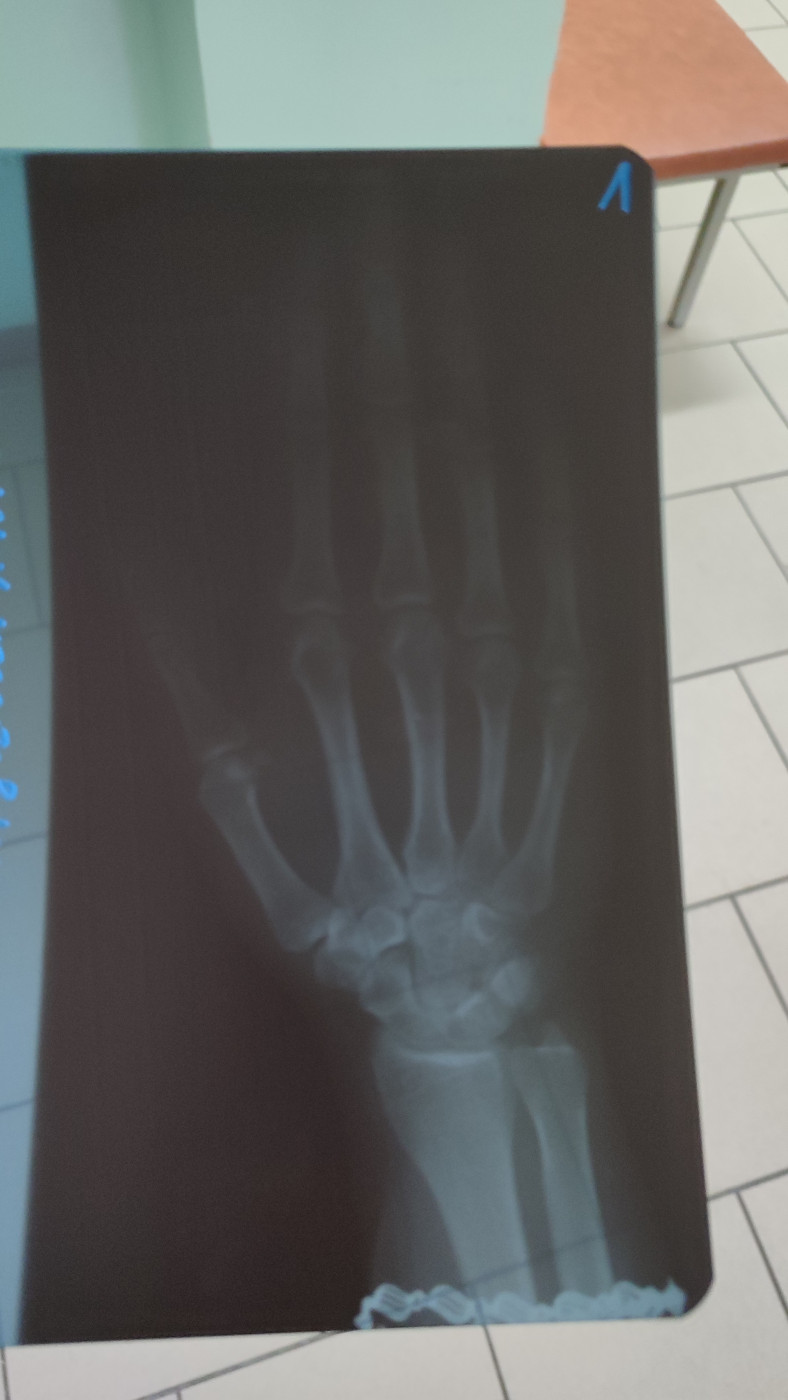

После удара по руке, болит уже второй месяц